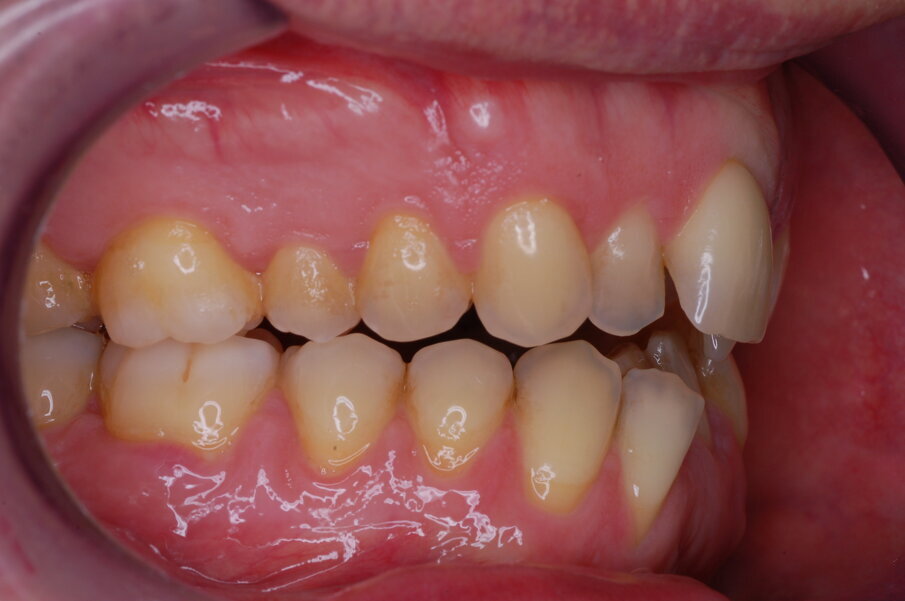

Diagnosi ed eziologia Un uomo sano di 39 anni si è presentato nel nostro studio ortodontico lamentando un aspetto dentale poco attraente e la paura della chirurgia ortognatica proposta da un altro ortodontista. Clinicamente, il profilo del paziente era rettilineo e la vista frontale non mostrava alcuna asimmetria facciale. L’esame funzionale non ha rivelato alcuna deviazione mandibolare o riduzione dei movimenti. Il paziente non aveva dolori articolari e non sono stati rilevati rumori articolari. Era presente una lieve occlusione molare bilaterale di Classe II, un morso aperto e un grave affollamento in entrambe le arcate. L’affollamento era particolarmente grave nell’arcata mandibolare, sebbene mancasse l’incisivo centrale mandibolare destro. Gli incisivi mascellari erano di piccole dimensioni, suggerendo una discrepanza dell’indice di Bolton se fossero stati presenti tutti e quattro gli incisivi mandibolari. Erano inoltre presenti un morso incrociato nella regione dell’incisivo laterale superiore sinistro e una grave rotazione distale del secondo premolare mandibolare sinistro (Figg. 1-8).

Figg. 1-8_Fotografie facciali e intraorali pre-trattamento.